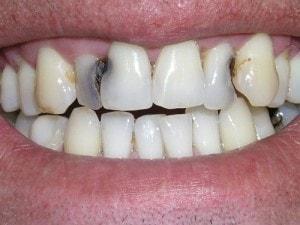

Caries in incisor teeth

Decay in teeth #'s 7, 8, and 10

Composite buildup

Tooth #7 is vital

Crown would require root canal and post for retention. Unfortunately, there is no ferrule for a crown.

Pre-opt incisal view